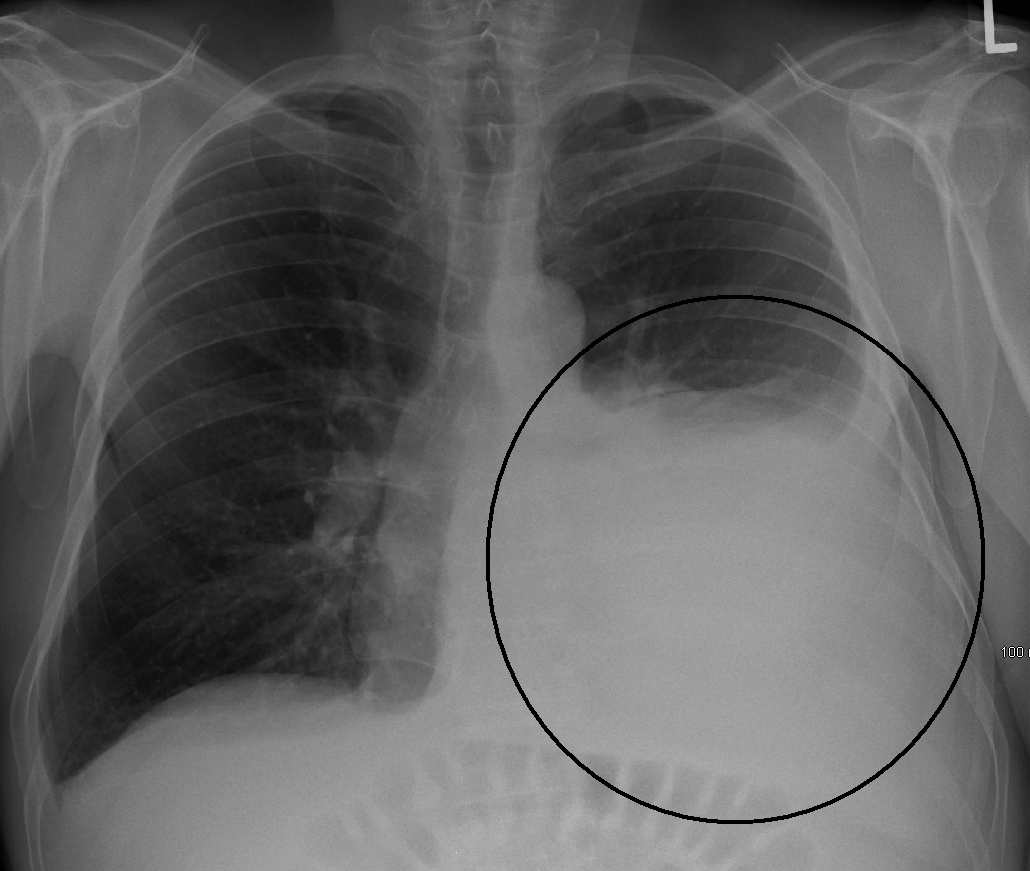

Pleural Effusion

Feature Description

Blunted costophrenic angle Loss of sharp angle between diaphragm and chest wall.

Fluid layering Horizontal fluid level, more evident on erect or decubitus views.

Meniscus sign Crescent-shaped opacity rising higher laterally than medially at the lung base.

Left-sided pleural effusion

Chest X-ray with a left-sided pleural effusion